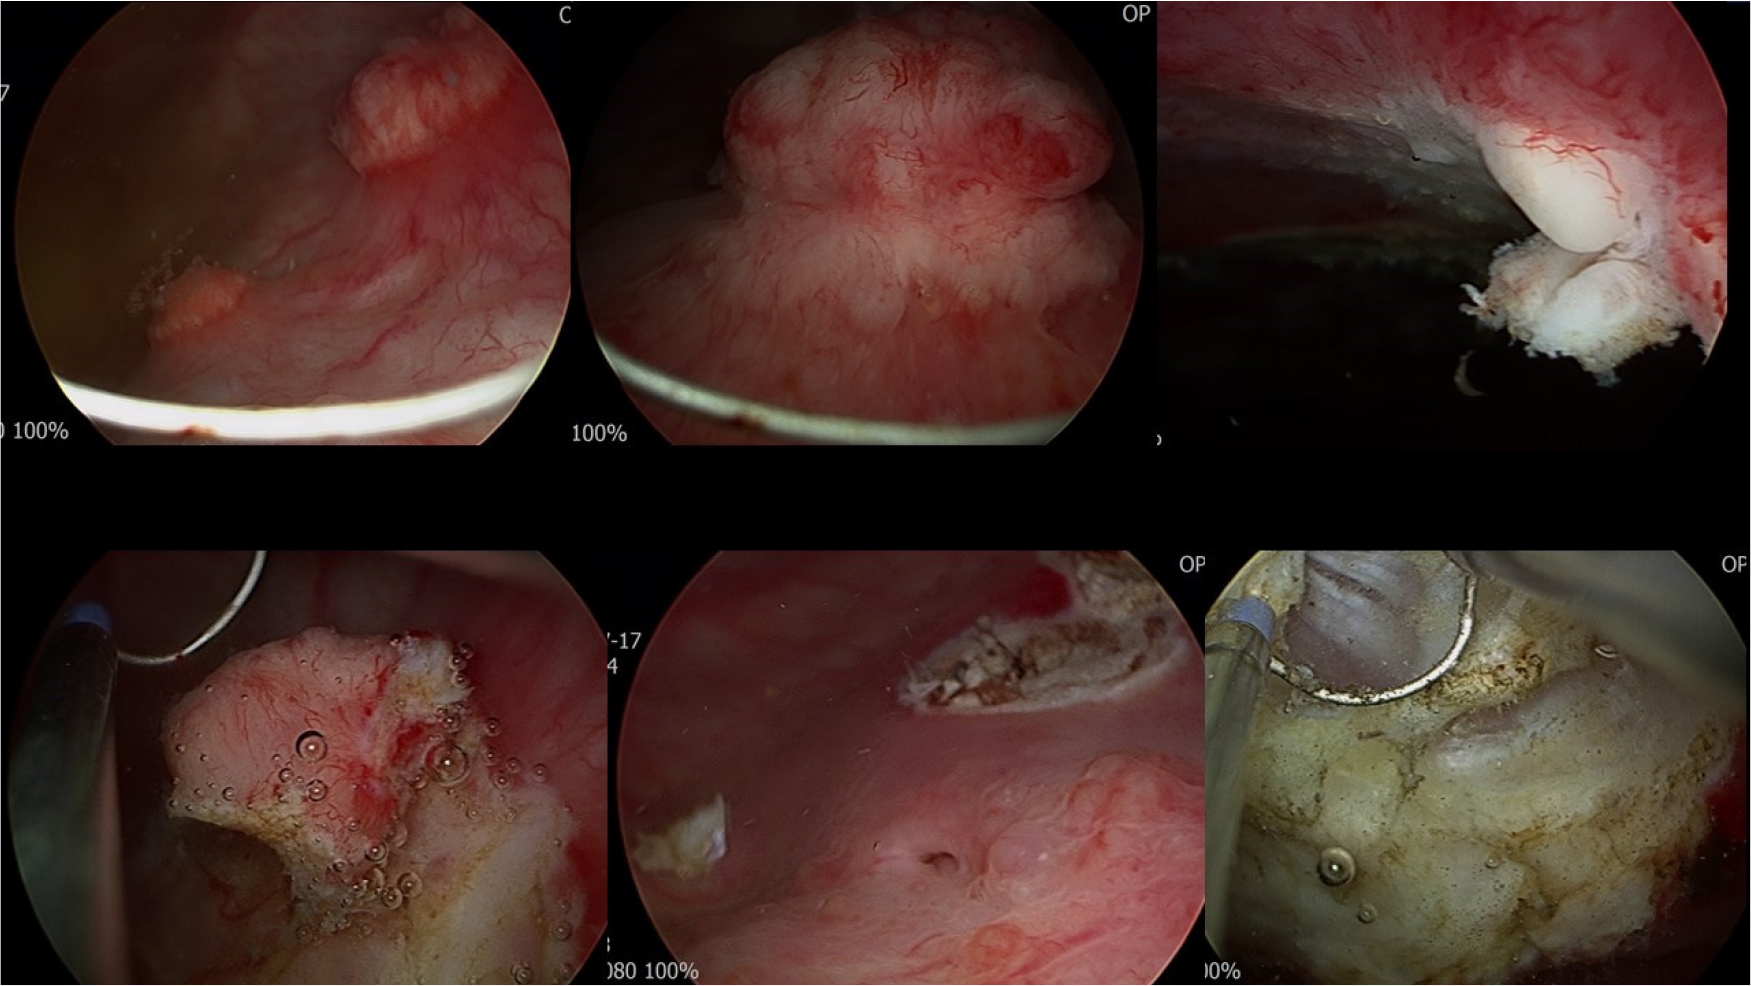

2.4. 방광 내시경

요도 및 요도 점막은 정상 소견이었으며 소변은 탁하여 시야가 좋지 않았다. 방광목, 방광의 양측벽, 삼각부, 후벽 및 전벽 등에 여러 개의 고형 종괴가 관찰되었다. 이는 일반적으로 보이는 방광암 소견(papillary or solid mass)과는 다르게 보였으며 염증성 병변으로 보이는 부분도 있었다. 초음파에서 확인한 바대로 종양의 크기는 0.5 cm에서 방광목을 가리고 있는 2 cm의 mass까지 다양하였으며 약 20개 이상의 병변이 있었다. 방광목을 가리는 큰 종괴가 주로 환자의 배뇨장애를 유발하는 것으로 판단되었다.

▶ 방광경으로 시행한 조직검사(cold cup biopsy)에서 황색육아종성 방광염(xanthogranulomatous cystitis)의 가능성이 높다는 소견이었다. 양성 종양으로 판단되고 확진을 위해 환자와 상의하여 경요도 방광 종양 절제술을 시행하기로 하였다.

2.6. 경요도 방광 종양 절제술

충분히 경험적 항생제를 투여하여 균이 음전 된 것을 확인한 후 경요도방광종양절제술을 시행하였다. 종물은 granuloma 양상을 띄고 있었다. 방광을 2/3 정도 충만시킨 상태에서 절제술을 시행하였으며 이후 방광의 천공이나 요관입구의 손상이 없음을 확인하였다. 도뇨관은 2일간 삽입하였다.